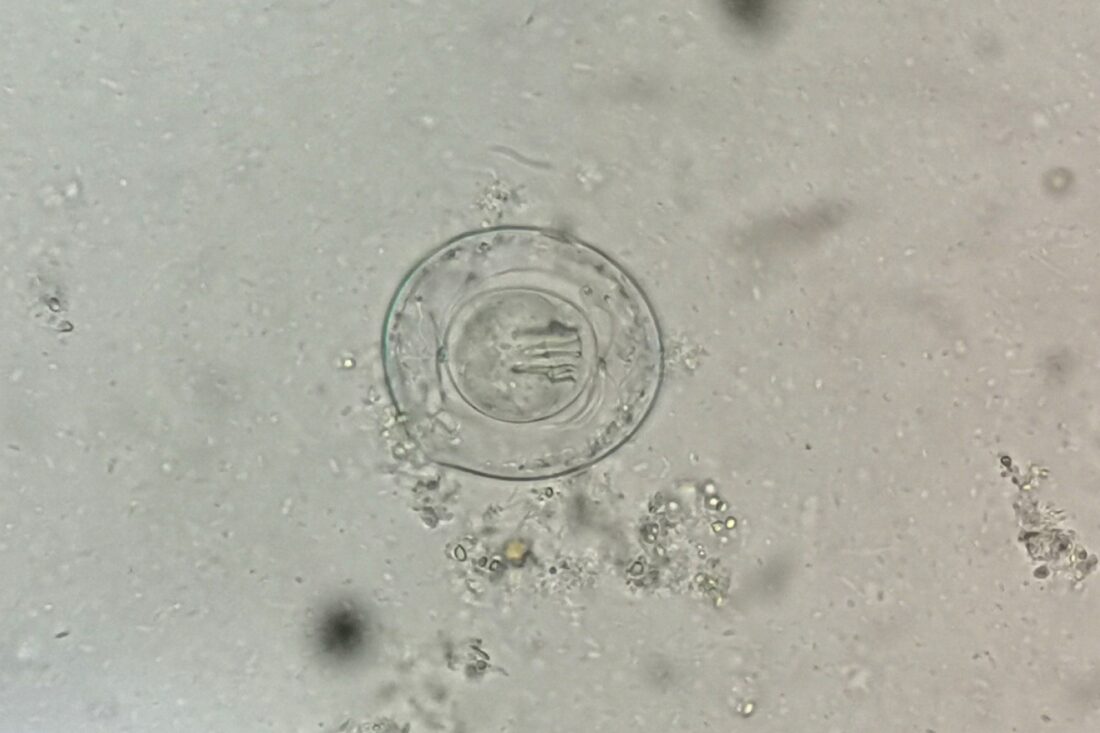

Description: Rodeado por una membrana perfectamente delineada, observamos un huevo del más pequeño de los céstodos humanos: Hymenolepis nana. Es visible las estructuras características como los filamentos en forma de mechón que salen de los polos de la membrana interna y en el interior la oncosfera provista de tres pares de ganchos. Este huevo no solo es una evidencia diagnóstica, sino un testimonio de adaptación biológica en su máxima expresión. Su simetría, translucidez y detalles internos lo convierten en una joya microscópica que combina ciencia, arte y complejidad evolutiva. Lo que parece una esfera minúscula es, en realidad, el principio de una interacción silenciosa entre huésped y parásito, es aquí donde la parasitología cobra vida ante nuestros ojos. Fotografía tomada en el Laboratorio de Microbiología, Universidad Autónoma de Chiriquí. Equipo utilizado: Microscopio óptico marca Numak, modelo XSZ 107 BN. Objetivo de 40x. Escala: entre 30 y 47 μm de diámetro.